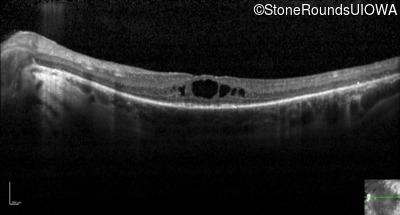

Optical Coherence Tomography - Right - 20/60 -1

Exemplar / OCT Stack